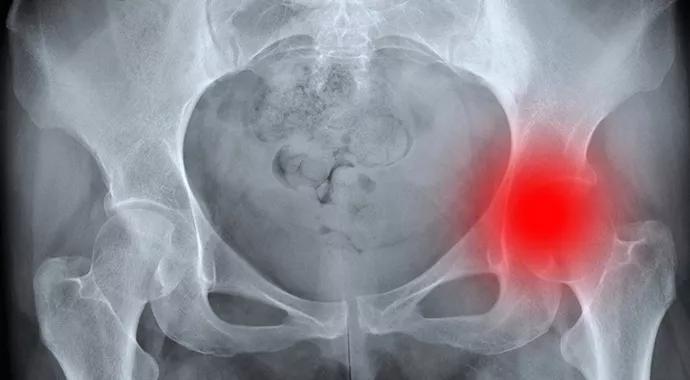

Anterior Approach to Total Hip Arthroplasty Offers Benefits

Faster recovery with less pain, muscle damage

Total hip arthroplasty is considered one of the most successful procedures of our modern surgical era. It improves quality of life, has an excellent success rate, relieves pain and restores mobility. We have found that using an anterior approach to total hip arthroplasty minimizes tissue damage and pain, and leads to a quicker recovery. The majority of hip arthroplasty procedures have used a posterior approach. The direct anterior approach to hip arthroplasty, first described in 1917, was not used extensively until recently due to technical concerns and the experience required.